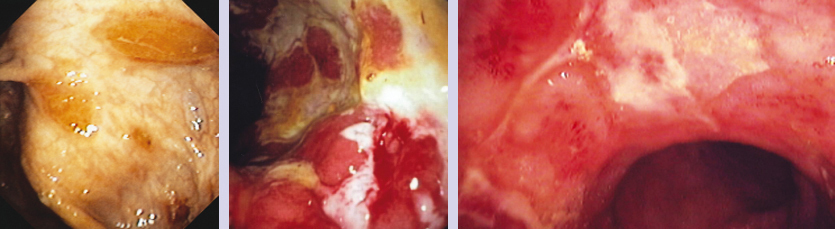

Maladie de Crohn

Endoscopie avec aspects évocateurs de maladie de Crohn